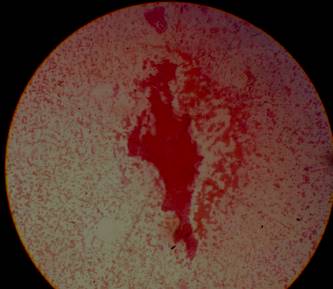

Centellograma paratiroideo con Spect CT: área de hipercaptación anormal del MIBI localizada en la proyección del tercio inferior del lóbulo tiroides izquierdo con extensión posterior e inferior. En suma: imagen nodular hipermetabólica compatible con un adenoma paratiroideo inferior izquierdo (figura 1).

Figura 1: Centellograma Spect CT que evidencia la hipercaptación paratiroidea.